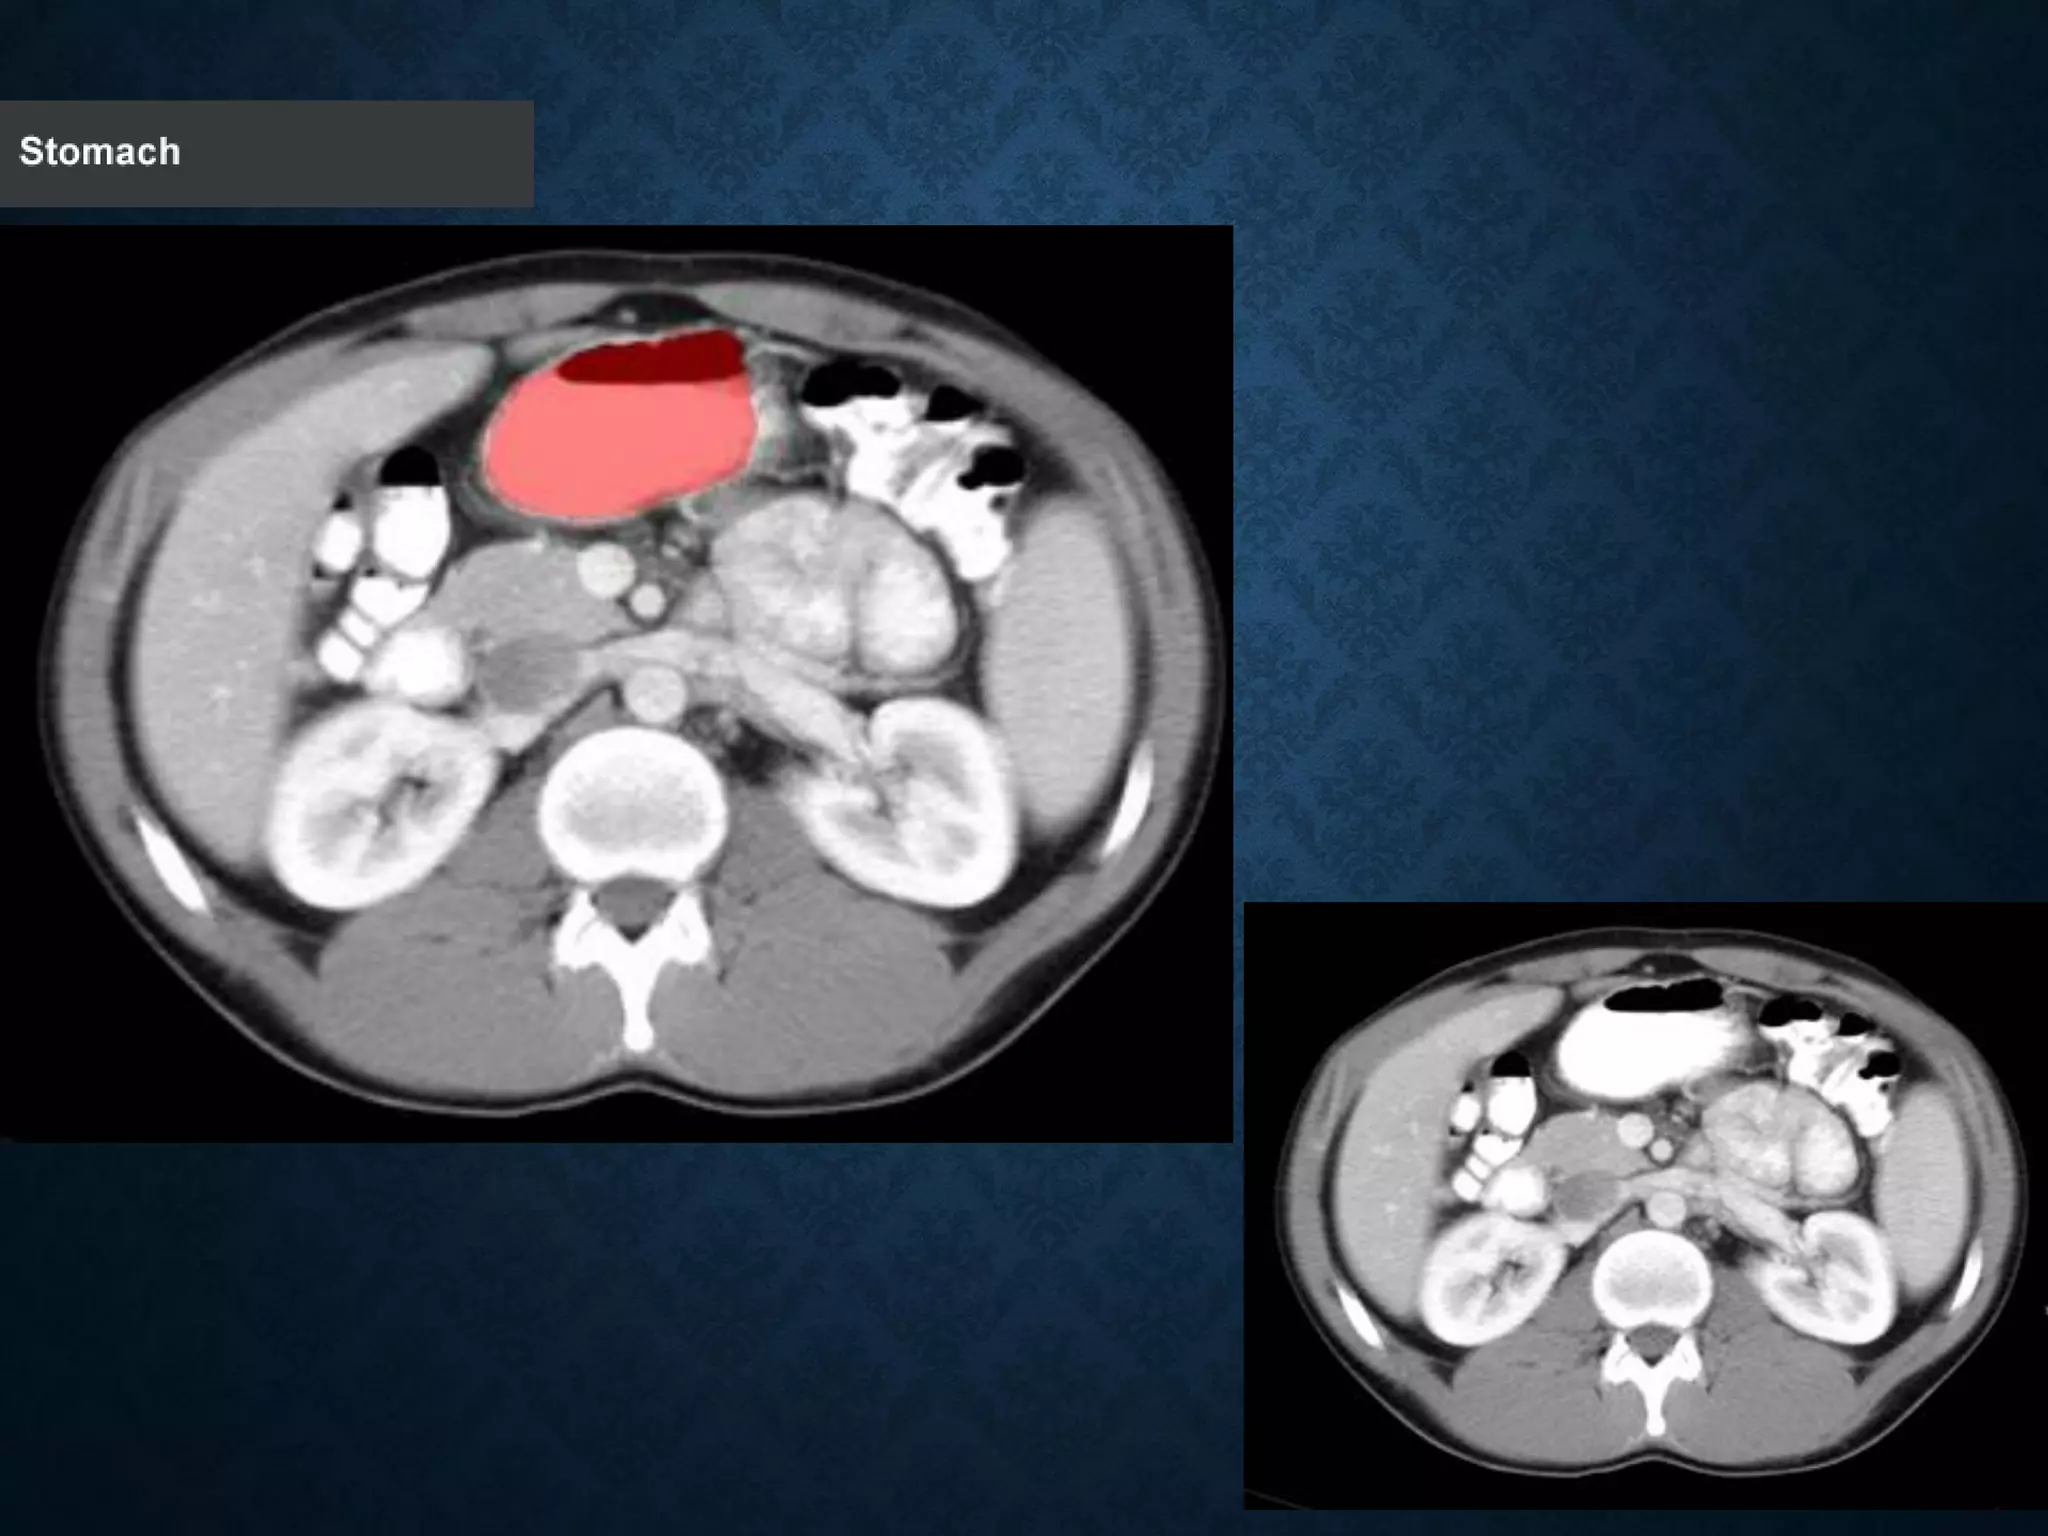

STOMACH

Identify the followingstructures in the body CT to the right. To view the location of the structure in the image click on the label at the left and the structure will be indicated in the image. Abdominal CT scans typically begin just above the diaphragm, so the first slice you see is of the lower chest.